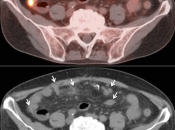

Peritoneal Carcinomatosis

Peritoneal carcinomatosis (dissemination of metastatic disease throughout portions of the peritoneal cavity) is most commonly associated with ovarian, pancreatic and GI malignancies.

When the CT images demonstrate multiple soft tissue lesions and the PET images show them to be FDG-avid, the diagnosis is readily apparent and made with confidence.

Occasionally, however, evidence of carcinomatosis is present on the PET images before visible lesions can be clearly identified on the non-contrast CT images.

Diagnosing and reporting peritoneal carcinomatosis solely from the PET images — without CT confirmation of the findings — can be unnerving, but is expected of the PET/CT radiologist.

Diagnosing carcinomatosis solely from the PET images requires a strong familiarity the typical sites of involvement:

- Serosal surfaces of liver & spleen

- Omentum (small nodules to omental caking)

- Paracolic gutters

- Peritoneal reflections

- Mesentery

- Serosal surfaces of the bowel

On rare occasion, non-Hodgkin lymphoma patients can present with peritoneal lymphomatosis, which appears exactly like carcinomatosis.